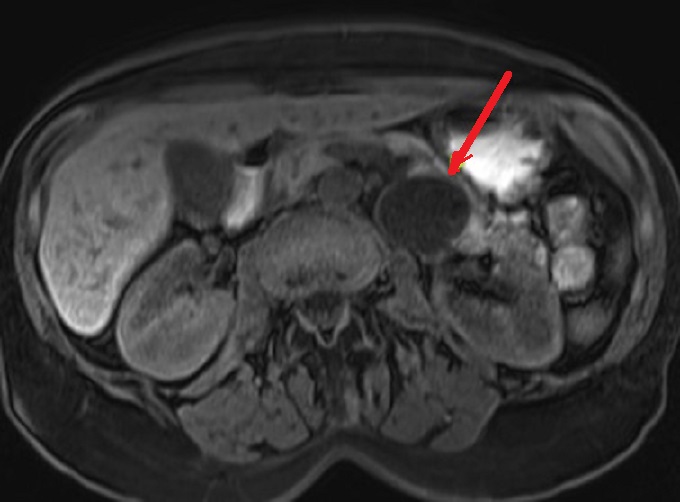

Image radiologique IRM d'une

cystarenome mucineux du pancreas avec aspect

lesionaire de kyste ovalaire uniloculaire a

hyposignal ( fleche rouge ) . Coupe axiale IRM

ponderee T1 |

Meme cas en coupe IRM axiale

ponderation T2 . La tumeur kydtique devient tres

hyperintense ( fleche rouge ) |

|